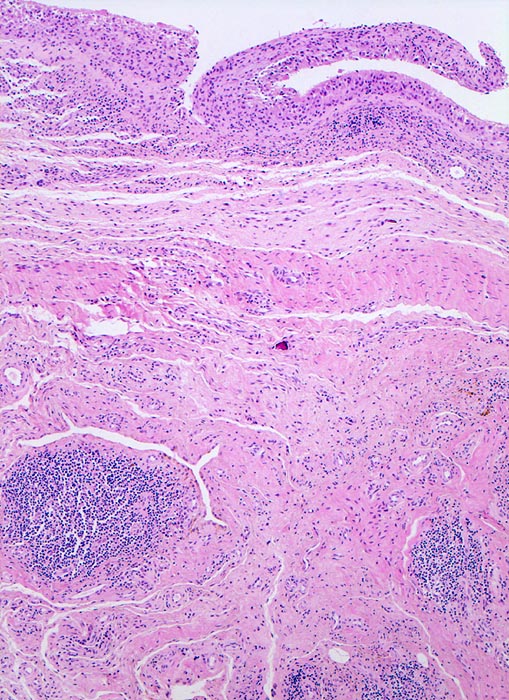

Basel 1MA/ Synovialitis bei rheumatoider Arthritis

Synovialitis bei rheumatoider Arthritis

In Abhängigkeit von der Entzündungsdauer werden unterschiedliche morphologische Befunde beschrieben. Die initiale proliferative Phase ist charakterisiert durch eine Hyperplasie der Synovialis, Fibrinexsudate und Gelenkergüsse. In der destruktiven Phase kommt es zur Zerstörung von Gelenkknorpel und gelenknahem Knochen durch Ausbildung eines intraartikulären Pannusgewebes (> 194). Die ausgebrannte Phase ist gekennzeichnet durch eine synoviale Fibrose mit zunehmender Ankylose (= Gelenkversteifung).

Typische histologische Veränderungen sind eine synoviale Zottenhyperplasie, Verbreiterung der Deckzellschicht unter Einschluss mehrkerniger Riesenzellen, Fibrinexsudate und synoviale Ulzerationen, Infiltrate von Lymphozyten teils in Form von Lymphfollikeln, Plasmazellen, neutrophilen Granulozyten, Makrophagen und Siderophagen, sowie Einschlüsse von Knorpel- und Knochenfragmenten (Detritussynovialitis). Die histologischen Befunde der Synovialis korrelieren oft nicht mit den klinischen Angaben. Trotz fortgeschrittener Gelenkdestruktion mit ausgeprägter klinischer Symptomatik können Synovialektomiepräparate nur sehr geringe pathologische Veränderungen zeigen. Oft ist auch nicht mehr zu eruieren, welche Läsionen Folge der Grundkrankheit und welche Folge diverser intraartikulärer Therapien oder begleitender Superinfektionen sind.

• Synovialis mit verplumpten Zotten.

• Stark proliferierte mehrreihige synoviale Deckzellschicht.

• Herdförmig Fibrinauflagerungen durchsetzt von neutrophilen Granulozyten.

• Hyperzelluläres Stroma mit lymphoplasmazellulärem Entzündungsinfiltrat mit Ausbildung von Lymphfollikeln.